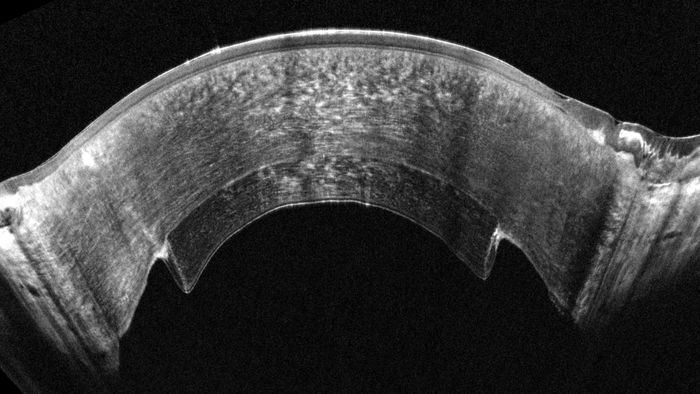

OCULUS Pentacam® Cornea OCT - The best of both worlds: Scheimpflug and OCT

In just one second, it provides cornea specialists with both a Scheimpflug image of the anterior segment and OCT images of the cornea, all in a single, efficient measurement, streamlining diagnostics while enhancing clinical precision.

- Simultaneous 360° 3D capture using Scheimpflug imaging and corneal OCT

- Ultra-high resolution of 1.9μm across the entire cornea